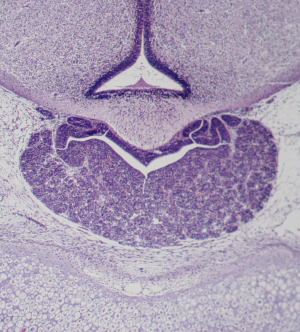

Stage 23

CfS 23

d41-44